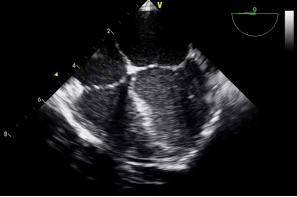

3.经胃底部(图6):距门齿50cm,左室乳头肌短轴观、二尖瓣短轴观、经胃底左室长轴观、经胃底右室流入道观等。

胃底 左室乳头肌短轴(图6)